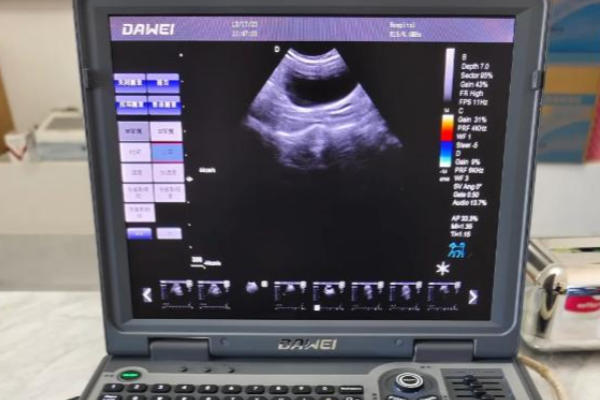

阴道超声,是将一个套有消毒避孕套、涂有耦合剂的细长探头,经阴道置入,贴近子宫和卵巢进行观察的检查。

主要感觉:绝大多数女性感受到的是一种冰冷的、有压力的、轻微的撑胀感。耦合剂和润滑剂会让探头顺利进入,操作医生也会动作轻柔。对于没有严重妇科炎症、阴道痉挛或特殊解剖结构异常的女性来说,这种不适感通常是短暂且完全可以忍受的。